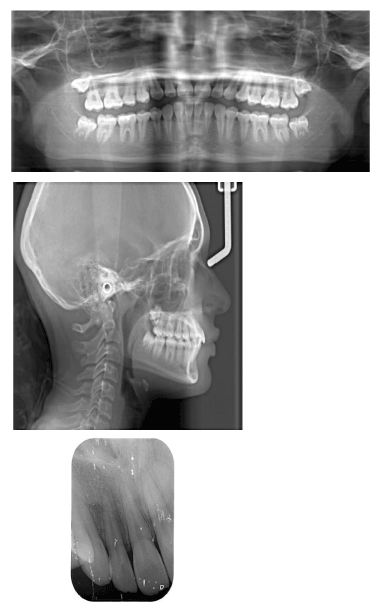

A 12-year-old female came to the dental clinic in the private sector with a chief complaint of unpleasant smile as the upper lateral incisor is flared and missed upper right canine. During our discussion with the patient, her humble request was not to lose any of the permanent teeth. On clinical examination, it’s found that #12 is labially proclined, retained upper right primary canine with slight soft tissue elevation in the labial sulcus on palpation. Intraoral photographs showed misalignment of teeth with shifted upper midline to the right side (Figure 1). A poor oral hygiene had been noticed with a generalized mild upper and lower gingivitis. Panoramic radiograph showed impacted #13 which is overlapping the apical 1/3 of the lateral incisor with retained primary canine (Figure 2). The mesial surface of the canine is passing the root of the lateral and almost flushing with distal surface of the apical third of the central incisor. Periapical radiograph in different horizontal directions (SLOB) techniques along with the palpation and the labial proclination of the lateral incisor confirmed that the impacted canine is labially located. Lateral cephalogram revealed that the incisal edge of the canine is labial to the roots of the incisors. Cephalography analysis documented that patient has skeletal class I malocclusion with decreased anterior facial height and relatively proclined upper and lower incisors. The soft tissue analysis showed that upper and lower lips are relatively behind the Esthetic line (E-line) by 4mm for the upper and 3.6mm for the lower (Table 1).

0.022 slot Roth brackets had been bonded on all upper and lower teeth except #12 which acted as a free body initially till the canine had been moved away from its root (Figure 3). After 6 months of alignment, space started to be created for the canine using opening coil spring (0.010 x 0.035 inch) (Figure 4). The first stage of surgery was planned to be VISTA technique in order to move the canine horizontally and to situate the canine crown directly under its socket using the microimplant (MI) (Figures 5 and 6). During surgery, all the bone distal to the canine crown till its CEJ which is in the way of its movement had been removed. A microimplant from (Ormco) VectorTas of 2 x 8 mm had been placed in the infrazygomatic crest parallel to the upper right first molar (Figure 7). A lingual button bonded on the labial surface of the canine and connected to the microimplant via a power chain which was passing under the alveolar mucosa over the canine. The horizontal movement of the crown had been activated every month by cutting a hole from the power chain. A panoramic periapical radiograph A-B taken directly after MI placement and 3 months over that to control the movement of the canine (Figures 8 and 9). After 3 months of horizontal movement of the canine, the patient referred again for the 2nd stage of surgery where a full reflected flap performed in order to remove the old power chain and place new one which is directly connected to the main archwire (Figure 10). All the bone above the canine crown till the 2 mm from the alveolar crest had been removed in order to facilitate the tooth movement vertically. The main arch wire which is 0.017x0.025 Stst had been offset in the area between #12, 14 (Figure 11). This offset placed to help for keeping the canine root in the alveolar bone and avoid the labial tipping of the crown. A crimpable attachment with a hook fixed on the wire directly over the canine crown and a power chain connected directly from the lingual button to the hook (Figure 12). The vertical movement of the crown had been activated every month by cutting a hole from the power chain. After the canine came out of the soft tissue a bracket bonded and thin wire placed in its slot with a sequence of 0.12 Niti, 0.14 Niti, 0.16 Niti, 0.16 x 0.22 Niti, 0.16 x 0.22 Stst, 0.17 x 0.25 Niti and 0.17 x 0.25 Stst. Canine root torque had been checked after its reaching to the occlusal plane and found that no need for any adjustment since it is similar with the opposing canine root eminence (Figure 13). After 24 months of active treatment, all appliances were debonded (Figure 14). Orthopantogram, lateral cephalography and periapical radiograph had been taken to record as a baseline for future follow up and assessment. Clear overlays delivered for both arches as retainers with proper instructions (Figure 15).

Figure 7. A panoramic radiograph shows the insertion of the micro implant and the button which had been to the labial surface of #13

Figure 8. A panoramic radiograph 3 months past traction #13

Figure 9. A- Intra oral radiograph immediately before horizontal movement of #13; B-3 months post traction #13